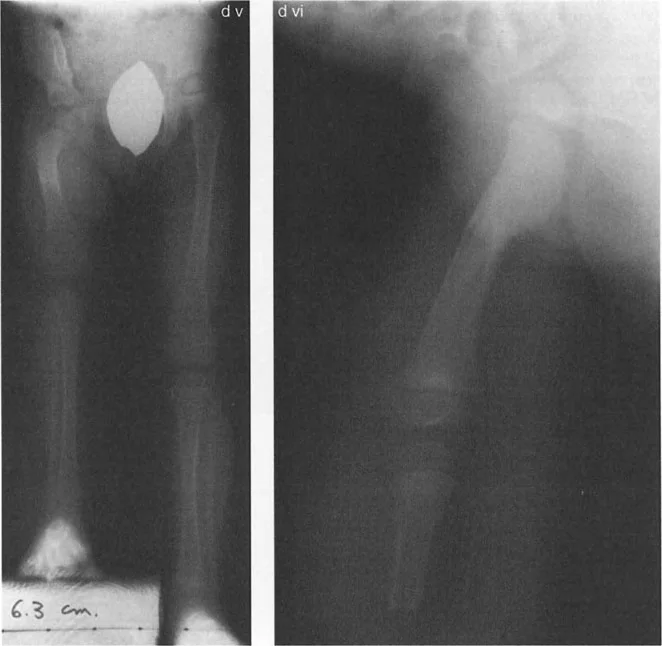

اختلاف طول الساق

في بعض التشوهات، قد يصبح هناك اختلاف ملحوظ في طول الساقين (Leg Length Discrepancy)، مما يؤثر على المشية ويسبب مشاكل في الظهر والركبة.

* تصحيح اختلاف طول الساق: إذا كان موجودًا.

• تأثير التقصير: تؤدي جراحة عظم الفخذ الروحاء إلى تقصير في طول الساق، مما يريح عضلات المقربة ويقلل الحاجة إلى بضع وتر المقربة.

تأثير التشوه على المدور الكبير